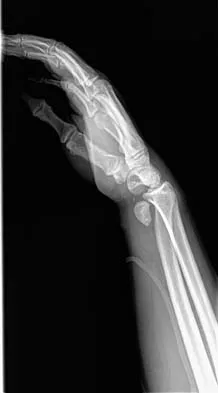

Question 50 High Yield

A 32-year-old man has intense right hand and wrist pain, a deformed wrist, and numbness in his fingers after falling off his motorcycle. This is an isolated injury. Examination reveals a swollen wrist, normal capillary refill to all fingers, and limited flexion of all fingers. Radiographs are shown in Figures 21a and 21b. Neurologic examination of the hand will most likely reveal

Detailed Explanation